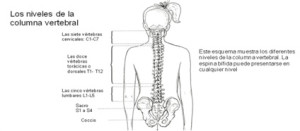

La espina Bifida puede presentarse en cualquier parte de la columna vertebral y es un defecto que ocurre al principio del embarazo en las primeras semanas (21 a 28 días) después de la concepción.

La mayoría de los defectos ocurren en el área lumbar inferior o sacra de la columna (las áreas más bajas de la espalda son las últimas en cerrarse durante la etapa embrionaria del desarrollo del tubo neural.)

El punto en la médula espinal donde ocurre el área subdesarrollada se llama el “nivel” de la espina bífida.

Cuanto más alto en la médula espinal está el “nivel”, mayor es el efecto sobre la función nerviosa normal.

Algunas personas con espina bífida en un nivel muy bajo pueden caminar con muy poca ayuda o sin ella mientras que aquellas que tienen un nivel más alto necesitarán aparatos ortopédicos para desplazarse y, si el nivel es muy alto, silla de ruedas.